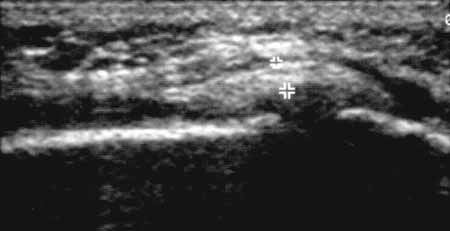

Рис. 9. Коленный сустав в норме. Внутренняя поверхность коленного сустава,

сагиттальная проекция; внутренняя (большеберцовая) коллатеральная связка (+).